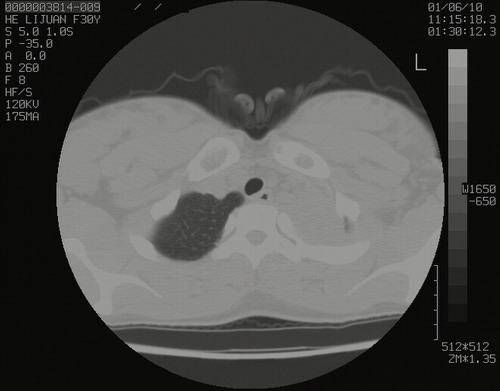

怀孕3个月时(2009-3至4月间),自述突感左侧前后胸疼痛1天,以前胸明显,随后偶感闷痛,余未见异

左肺尖脊柱旁沟肿块,境界清楚,边缘光滑,密度不均,内有多发点片状钙化,考虑良性肿瘤,骨软骨瘤或神经源性肿瘤可能,肺错构瘤不除外。

左后上纵隔见一类圆形肿块影,外侧边界清,密度不均匀,内可见点状钙化影,增强呈不均匀强化,考虑神经源性肿瘤可能。期待病理结果。